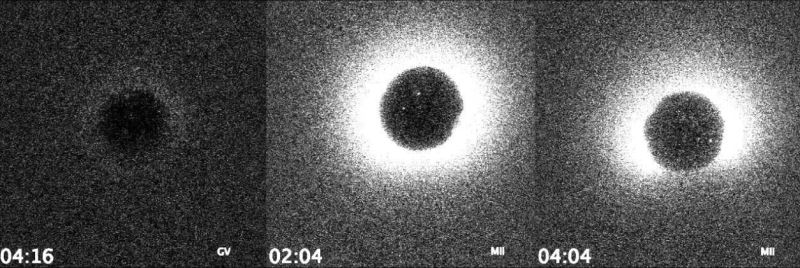

sperm yumurtaya dokunduğu anda, hücre bir anda çinko iyonlarını dışarı fırlatıyor ve bu sırada gözle görülmeyecek kadar küçük ama çok gerçek bir ışık patlaması oluşuyor.

daha da güzeli, bu parlamanın şiddeti, o yumurtadan sağlıklı bir embriyo oluşup oluşmayacağını bile gösterebiliyor. yani bilim insanı ışığa bakıp “bu olur” ya da “bunu geç” diyebiliyor. düşünün: hayat dediğiniz şey, mikrosaniyelik bir kıvılcımla başlıyor…